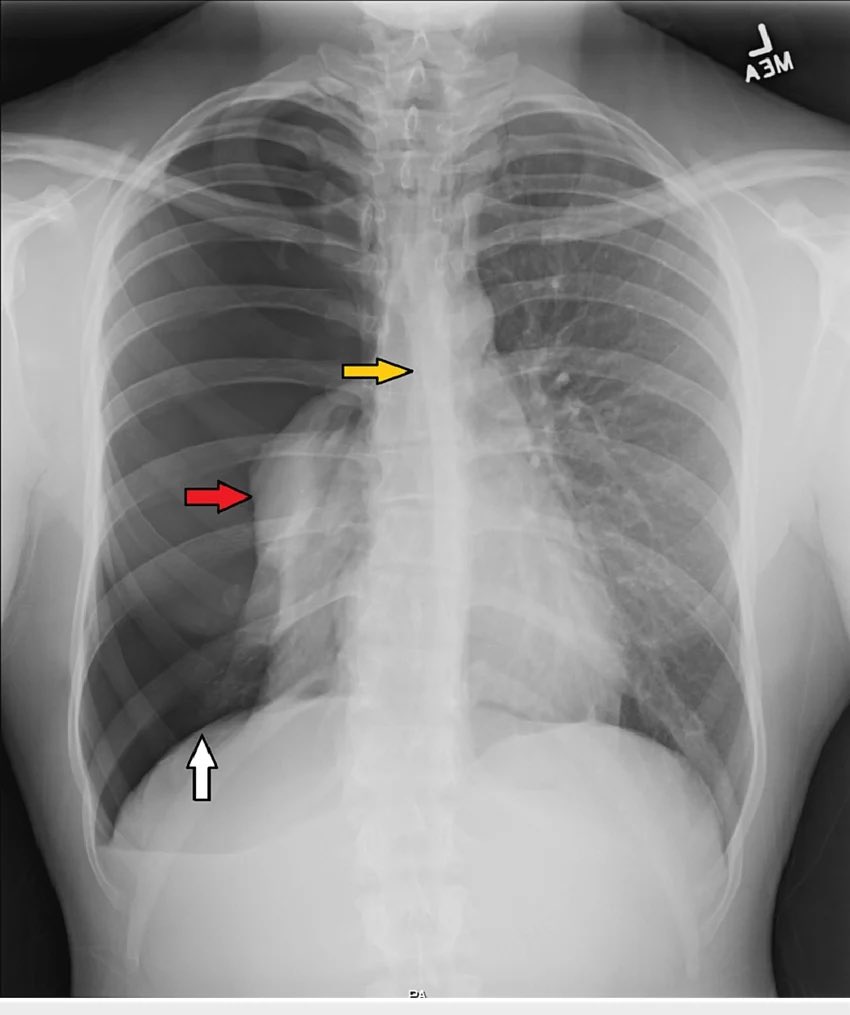

X-RAY QUIZ: Regarding this X-ray - the most likely diagnosis is…

A: Sarcoidosis

B: Mesothelioma

C: Pulmonary fibrosis

D: Thymoma

E: Primary bronchogenic lung carcinoma

Start Quiz bit.ly/3gU6LkX

Patient presents with acute onset dyspnea

Chest imaging findings ?!differential diagnoses ?!